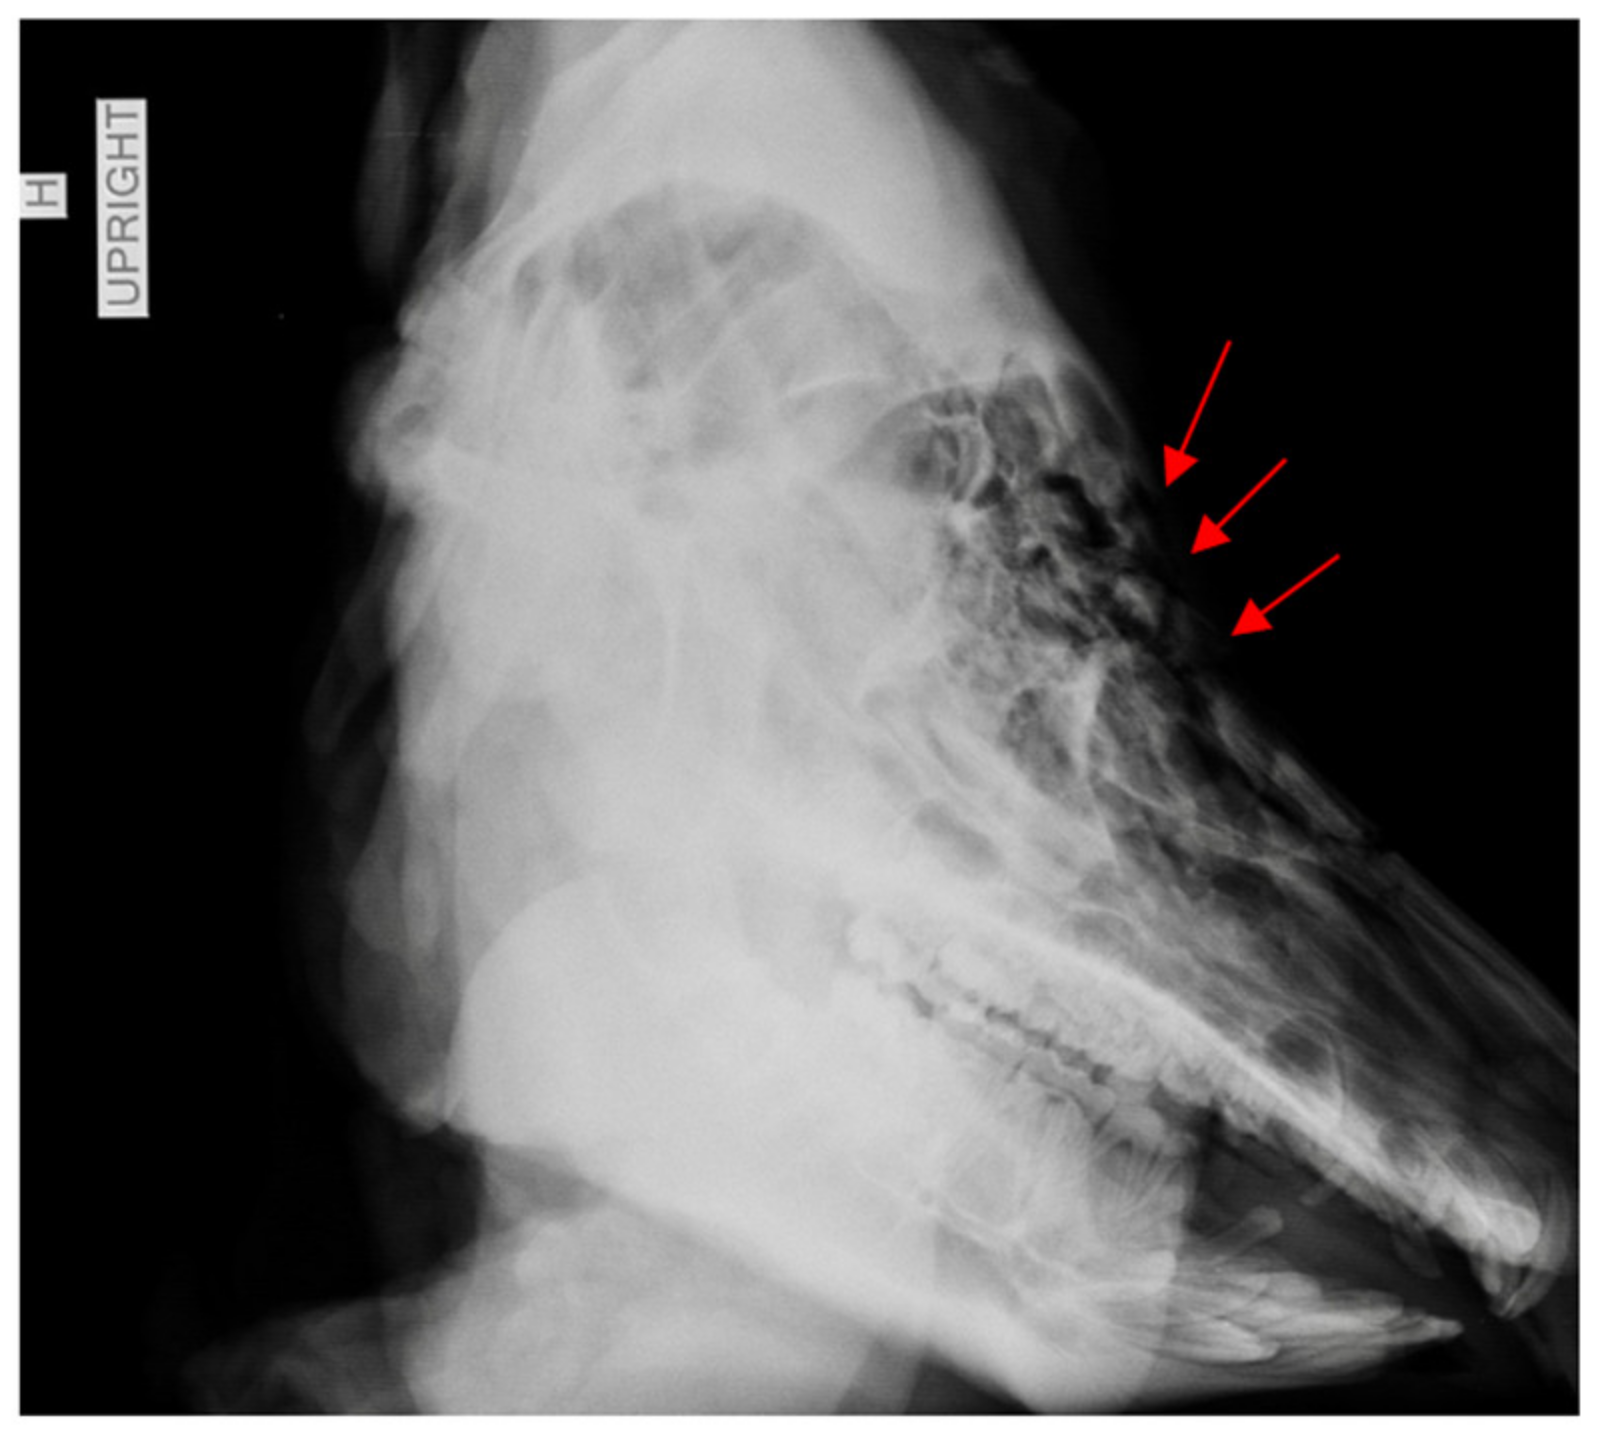

3. Results